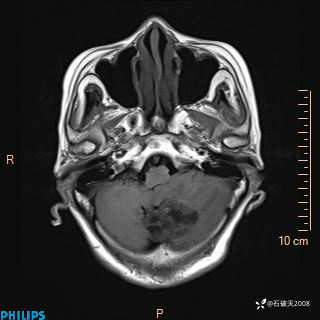

书上说这个肿瘤发生在幕下仅4.09%,你会想到它吗?(病理已公布)

女 86岁 主 诉:乏力1月

现病史:患者1月前活动出现双下肢乏力,无头晕、头痛、恶心、呕吐、肢体活动不利,休息后缓解,间断断发作,症状进行性加重,在家口服药物治疗(具体不详),效差,为进一步诊治,来我院,门诊按“乏力”收住我科,患者自发病以来,神志清,精神稍差,饮食睡眠欠佳,大小便正常,体重未见明显改变。

FLAIR